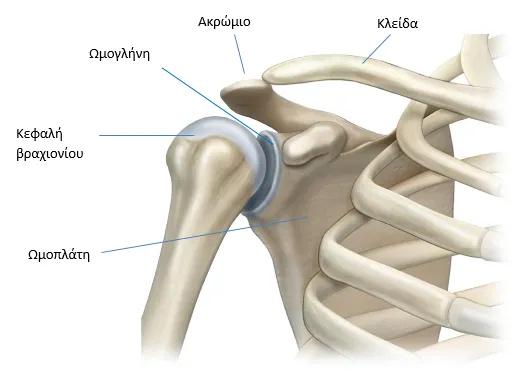

Ποια είναι τα μέρη του ώμου;

Η άρθρωση του ώμου αποτελείται από το οστό του άνω βραχίονα, την κλείδα και την ωμοπλάτη.

Περιλαμβάνει μύες, συνδέσμους, τένοντες και θυλάκους.

Όλα αυτά τα μέρη συνεργάζονται για να βοηθήσουν τον ώμο να κινείται άνετα προς διαφορετικές κατευθύνσεις.